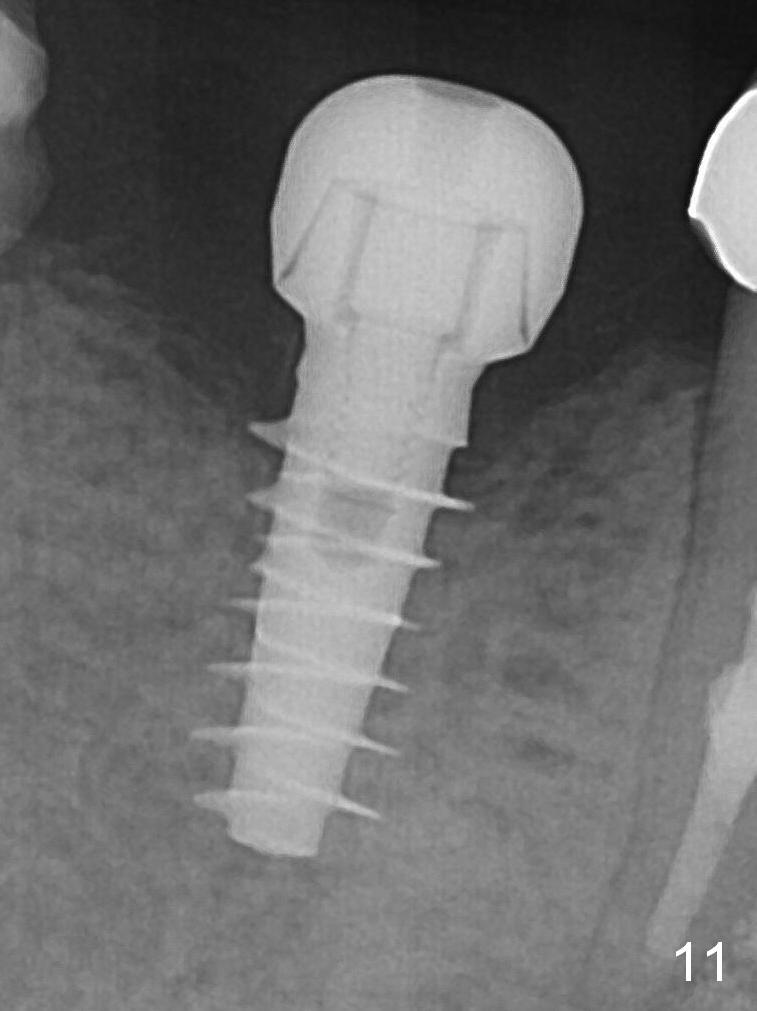

Splinted provisional is fabricated #30 and 31 one month postop. The patient returns for final restoration (single units) nearly 4 months postop (Fig.11). Since the margin is subgingival, please fabricate a screw type crown for #30.